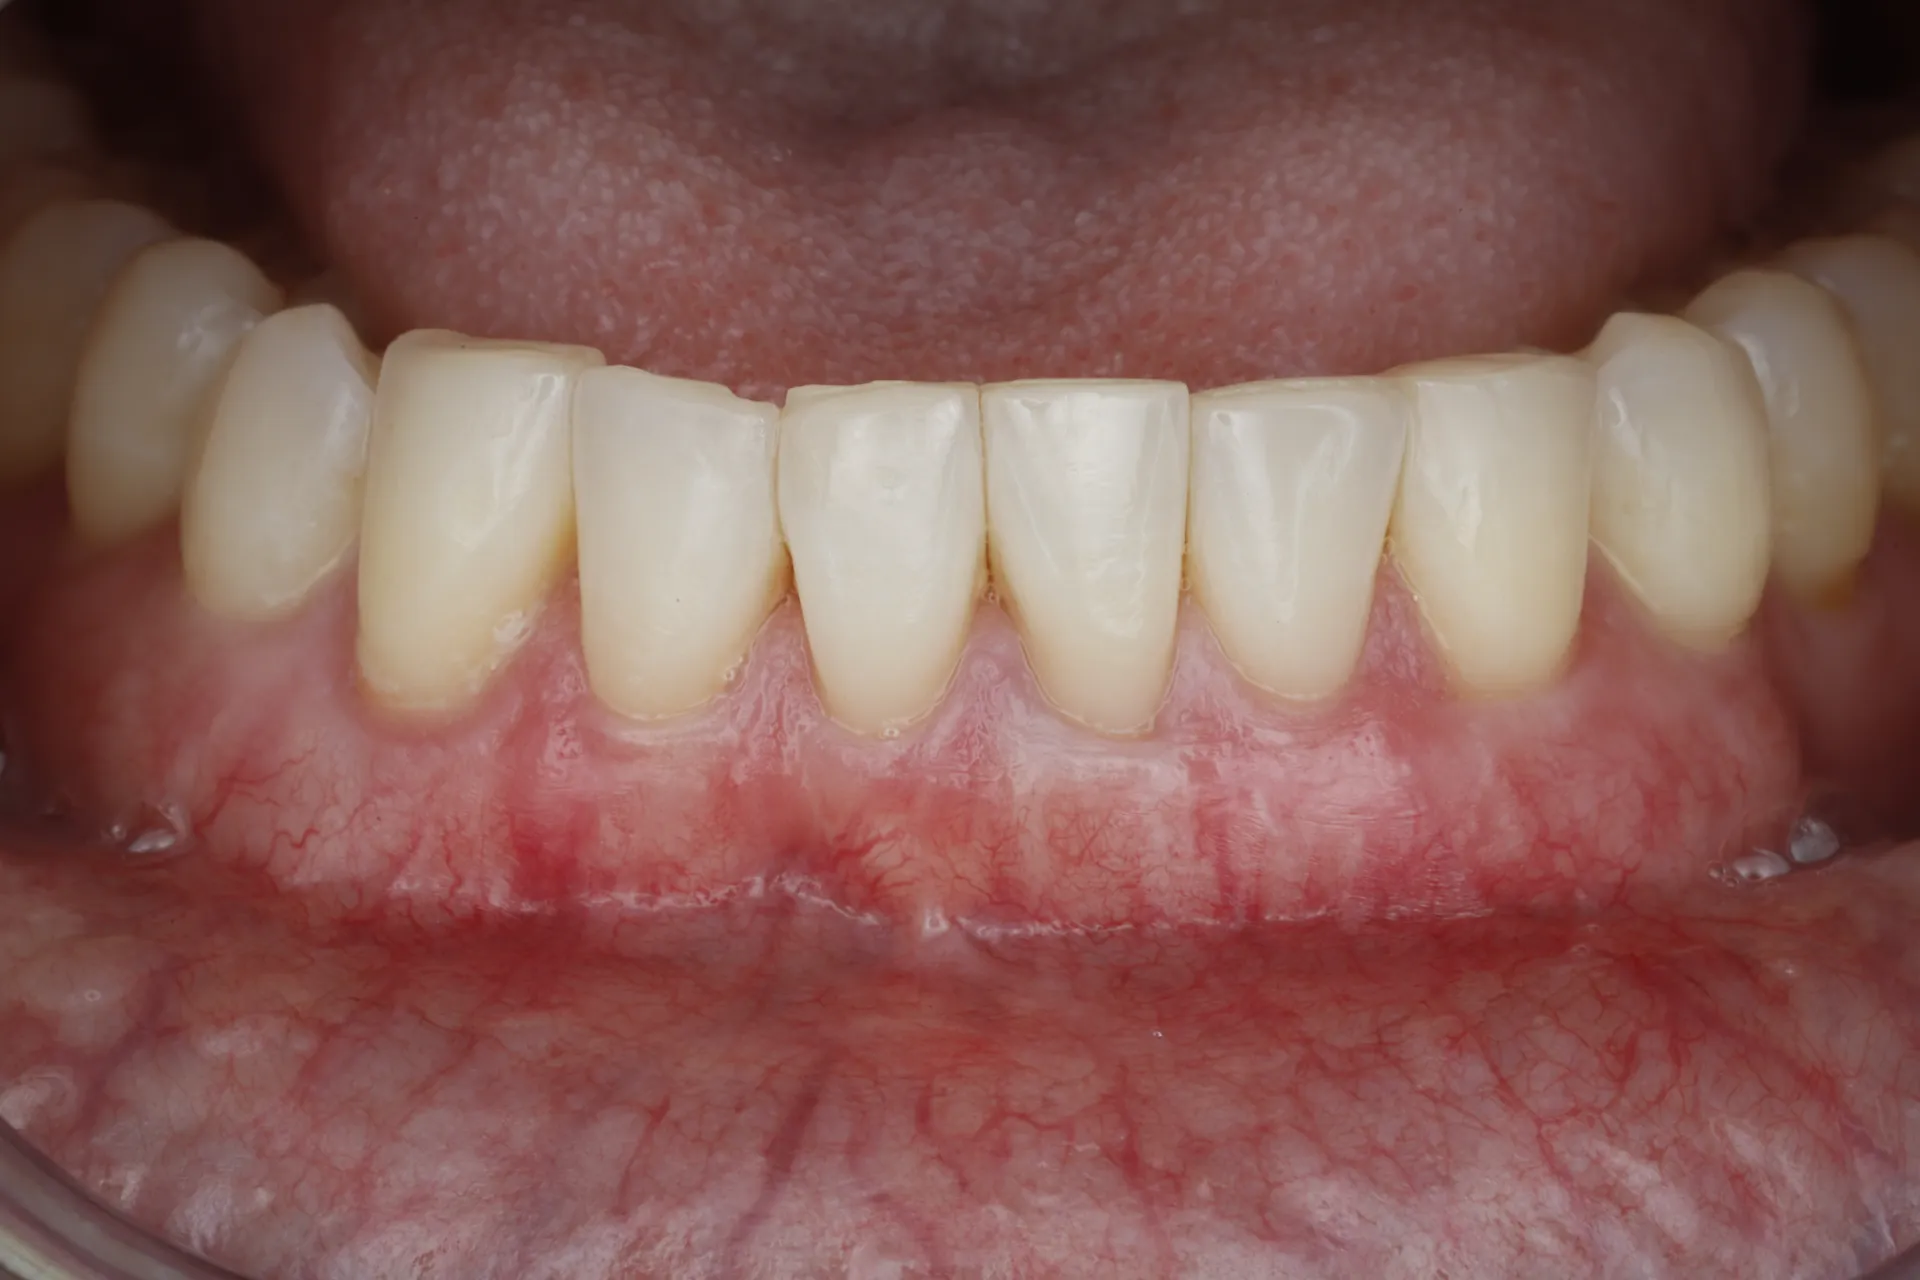

Gum Recession